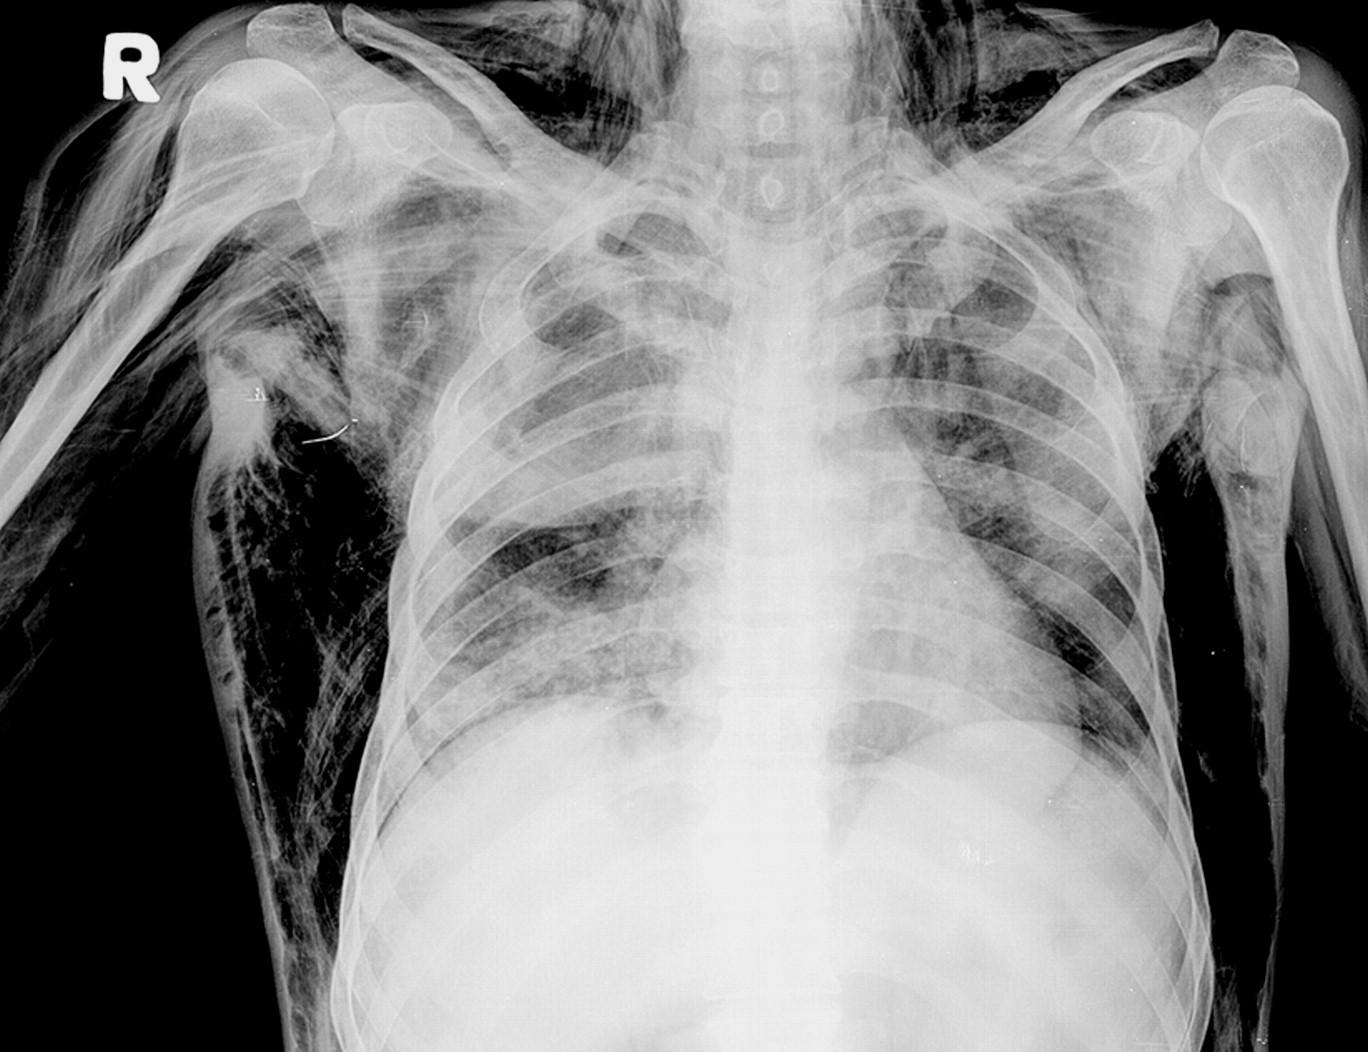

• Рентгенография. При патологиях ОГК делается обзорный снимок, по желанию - прицельный. Можно обнаружить переломы ребер, гемо- и пневмоторакс, пневмомедиастинум. При травмах лица делают рентгенограммы орбиты, костей носа и скуловой кости. Иногда требуется рентген черепа для исключения переломов его церебральной части.

Подкожная эмфизема на рентгенограмме.